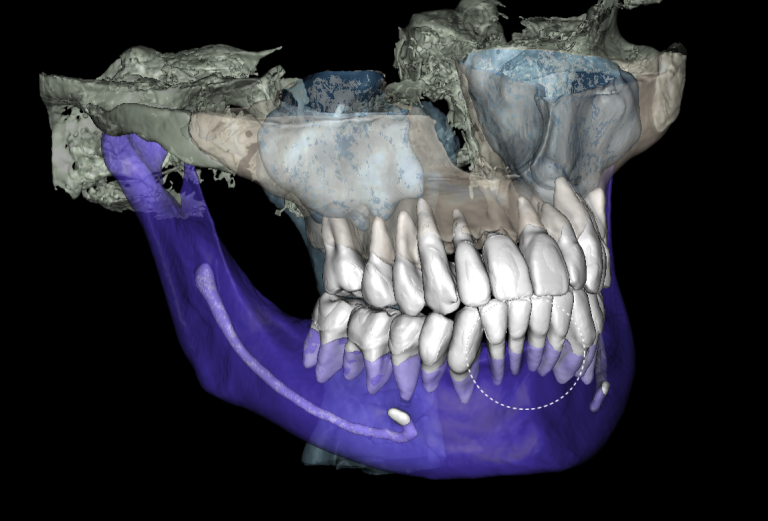

We start by loading the intraoral scan data into the Diagnocat STL module and getting a 3D model for choosing the optimal spatial position of the implant and planning the virtual design of the template for guided implant surgery